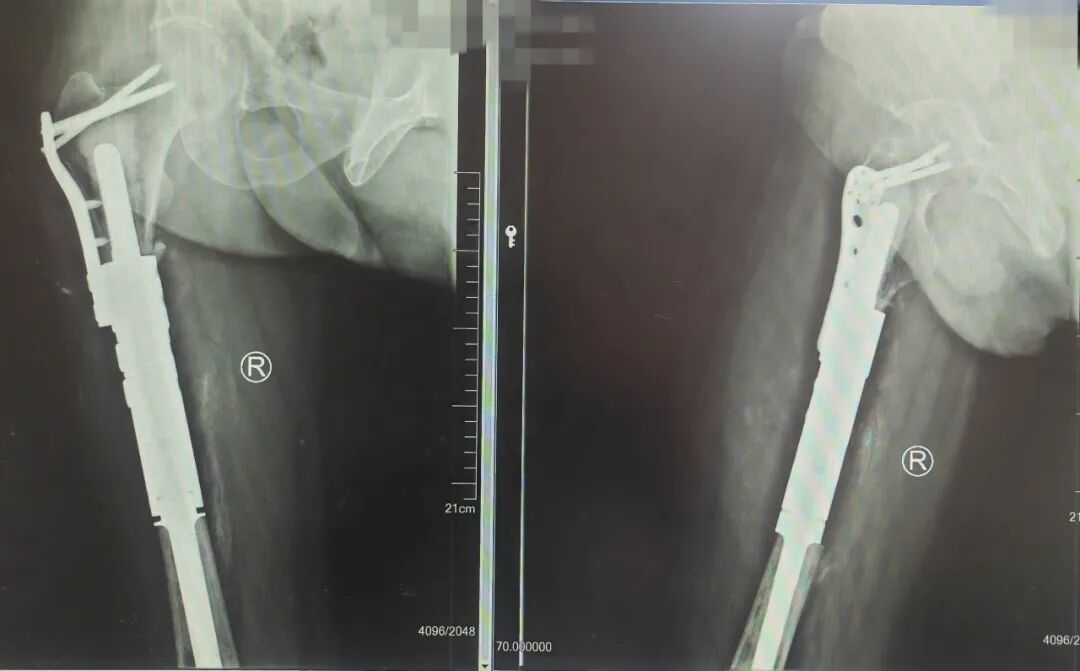

团队组织了多次跨学科研讨,全面评估其身体状况、免疫能力、麻醉风险及术后康复可能性,最终精心构思并准备了四套详尽的手术预案。每一套预案都反复推敲,权衡利弊,旨在万全之中寻求最优解,力求在根治当前急症、延长生存期与最大限度保障其未来生活质量、实现个人心愿之间,找到那个最精准、最温暖的平衡点。

经过周密的术前准备,手术得以顺利进行。然而,医疗团队的努力并未止步于手术室的成功。在为期两周半的住院治疗期间,医护团队的付出被患者看在眼里、记在心里。